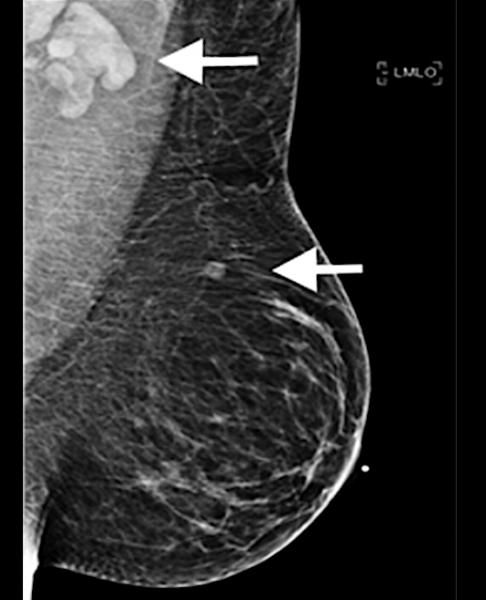

A 37-year-old woman developed a new, palpable left supraclavicular lymphadenopathy lump five days after her first dose of the Moderna COVID-19 vaccine in the left arm. On the day of vaccination, the patient was asymptomatic. This is an example of how the vaccine can mimic cancer and swollen lymph nodes. Read more about this case study. Image used with permission of RSNA.

Feature | Coronavirus (COVID-19) | April 09, 2021 | By Dave Fornell, Editor

While the mass COVID-19 vaccination effort over the past four months is bringing closer the light at the end of the...